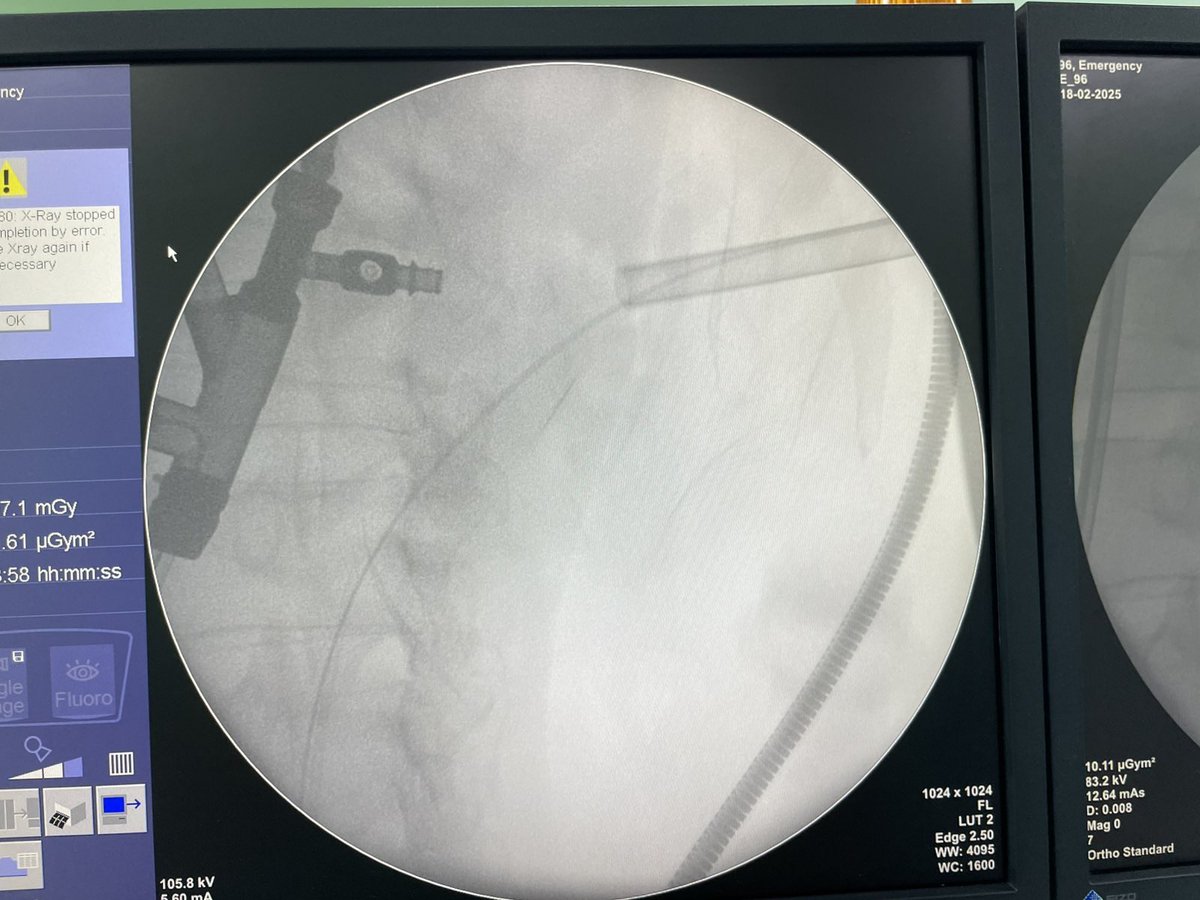

✅pre stented ➡️ good dilated ureter ❌ not always Pre and post ureteric evaluation is essential!! Endourological Society Endourology Academy APIS KidneyStone Institute, TFL EndoUrology Center Dr Parimal Gharia Saeed Bin Hamri #RIRS #FANS DrG